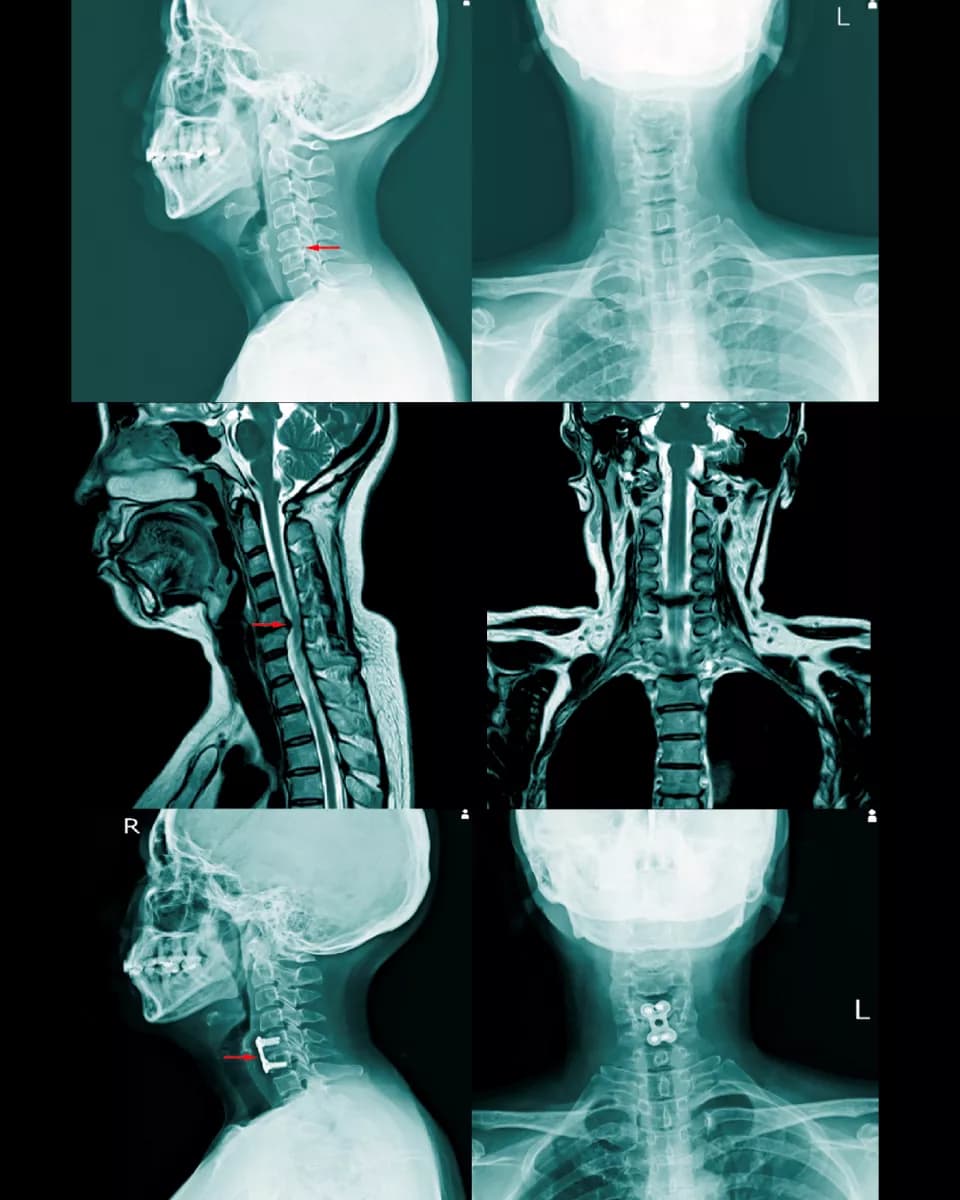

X-ray มาแล้วทำไมต้องตรวจ MRI อีก?

การตรวจด้วย X-ray ทั้ง 4 ท่าจะช่วยให้แพทย์ประเมินภาพรวมของโครงสร้างกระดูกได้อย่างละเอียด แต่ X-ray ไม่สามารถแสดงภาพของเนื้อเยื่ออ่อน (Soft Tissue) เช่น หมอนรองกระดูก เส้นประสาท และไขสันหลัง ได้อย่างชัดเจน

ดังนั้น การตรวจด้วย MRI จึงเข้ามาเติมเต็มในจุดนี้ โดยจะะให้ภาพที่มีความละเอียดสูงและสามารถเห็นรายละเอียดของเนื้อเยื่ออ่อนและลักษณะของรอยโรคได้อย่างชัดเจน ทำให้แพทย์สามารถ

- ระบุตำแหน่งและขนาดของรอยโรคได้อย่างแม่นยำ เช่น หมอนรองกระดูกปลิ้น หรือ หมอนรองกระดูกทับเส้นประสาท

- ประเมินความเสียหายของเส้นประสาท เห็นถึงระดับการกดทับของเส้นประสาทและไขสันหลัง

- วางแผนการรักษาได้อย่างถูกต้อง ช่วยให้แพทย์ตัดสินใจได้ว่าควรใช้วิธีการรักษาแบบไม่ผ่าตัด เช่น กายภาพบำบัด ทานยา หรือจำเป็นต้องผ่าตัด